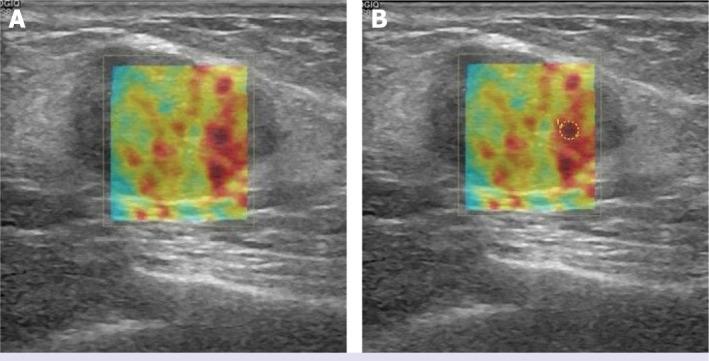

Myofibrolastoma of the breast (MFB) is a rare and benign stromal tumor. Although MFB is a benign entity, in radiologic evaluation, there is no specific diagnostic feature. Conventional breast imaging findings have been published before. Sonoelastography has been used as an imaging method that allows us to evaluate tissue stiffness in vivo and increases the specificity of B-mode ultrasonography in the discrimination of benign-malignant lesions. In this case report, it was shown that MFB is of high stiffness in shear wave elastography (SWE) evaluation. SWE findings of MFB, which is a benign lesion, have been described for the first time in the literature.

乳腺肌纤维母细胞瘤(MFB)是一种罕见的良性间质肿瘤。尽管MFB是良性病变,但在放射学评估中,没有特异性的诊断特征。常规乳腺影像学表现此前已有报道。超声弹性成像作为一种成像方法,能让我们在体内评估组织硬度,并提高B型超声在鉴别良恶性病变方面的特异性。在本病例报告中,显示出MFB在剪切波弹性成像(SWE)评估中具有高硬度。MFB作为一种良性病变的SWE表现,在文献中首次得到描述。